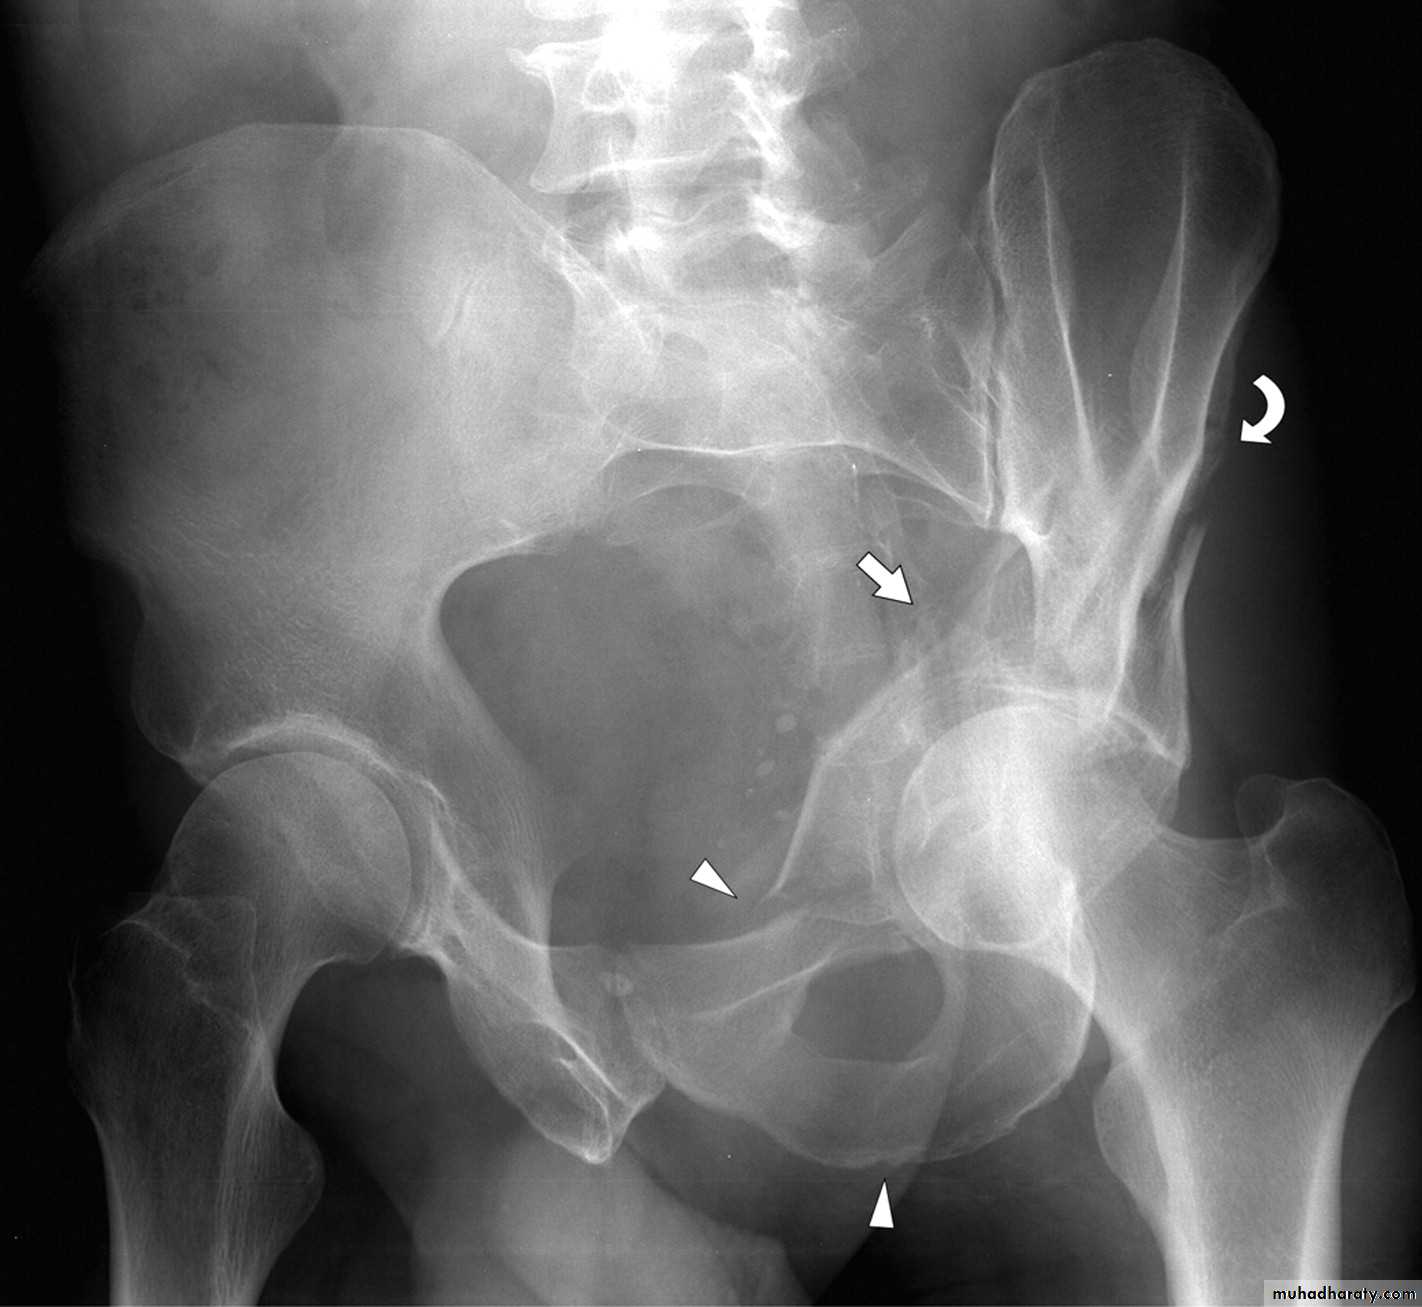

SCIATIC NERVE

Division of the main sciatic nerve is rare except.

in

gunshot wounds.

Traction lesions may occur with

traumatic hip dislocations

and with pelvic fractures.

Clinical features

In a complete lesion the hamstrings and all muscles

below the knee are paralysed;

the ankle jerk is absent.

Sensation is lost below the knee, except on the medial

side of the leg which is supplied by the saphenous

branch of the femoral nerve.

The patient walks with a

drop foot and

a high-stepping gait to avoid dragging the insensitive foot on the ground